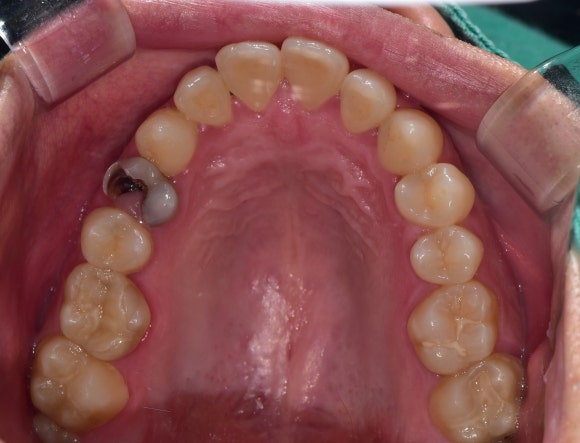

혼자서만 색깔이 다른 치아가 보이시지요?

치아 깨진 공간으로 잇몸들이 자라들어올 정도이니

얼마나 오랫동안 방치되었는지 알 수 있습니다.